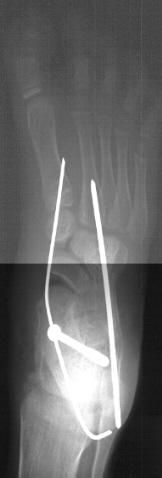

Some mechanism has to be used to correct the hindfoot valgus.. That was the case in this child in which subtalar arthrodesis with autograft bone graft and screw fixation was performed.